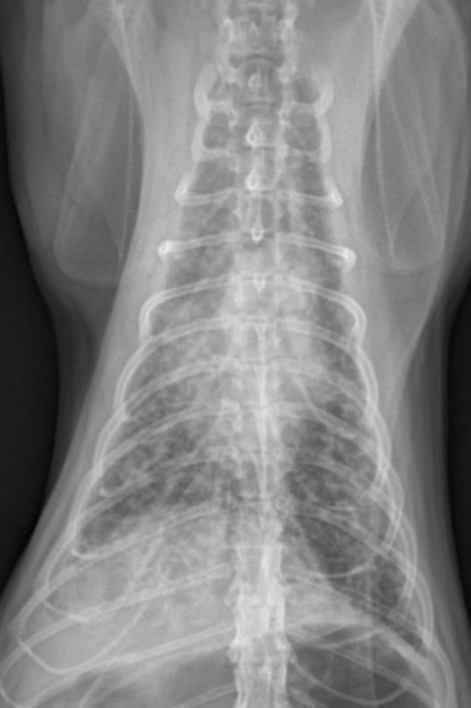

6️⃣ Bacterial Pneumonia (세균성 폐렴)

- 세균이 airway를 타고 들어가 폐에 감염 → 전엽, 중엽에서 많이 발생.

- air bronchogram(=alveolar pattern), bronchial pattern, lobar sign 보임

- Alveolar pattern : 가장 흔한 패턴 + consolidation

- Bronchial & interstitial markings : 종종 나타남.

- interstitial pattern alone : early or mild dz / 혈행성 감염.

- bronchial pattern alone : bronchial infection.